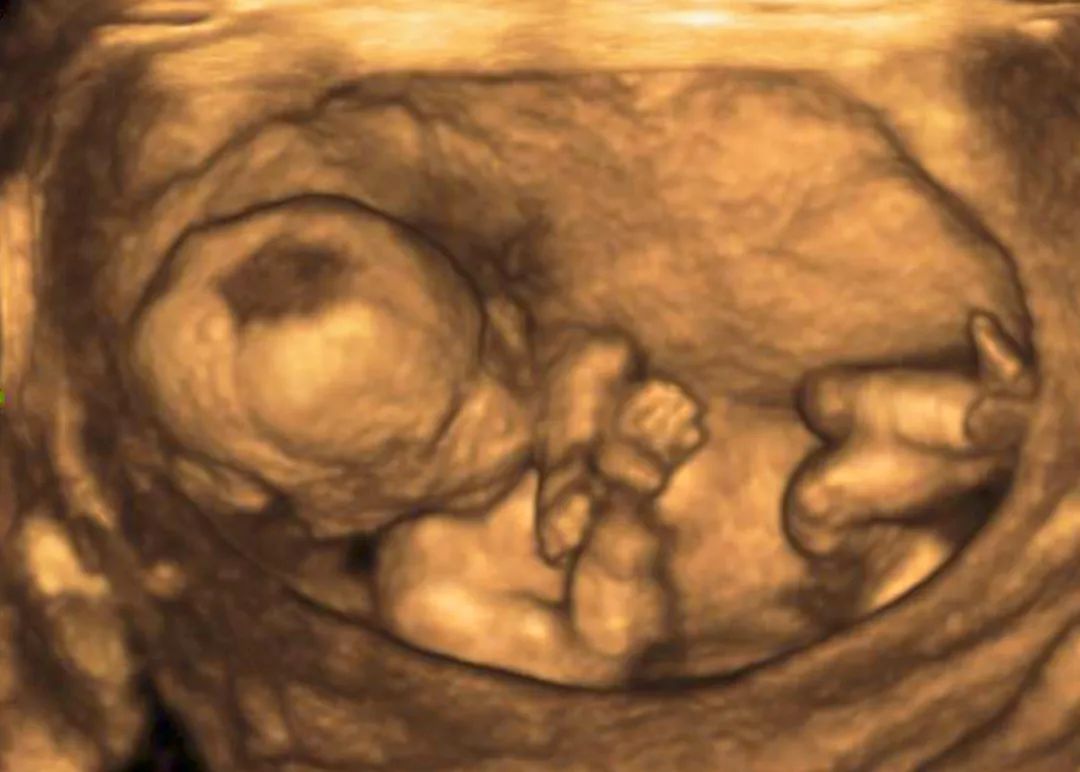

◆超声检查(6-7周就可以做了):监测孕囊位置、大小、数目及胎心情况,排除异位妊娠。

◆大畸形筛查:主要是通过B超检查宝宝是否患有严重的结构畸形。检查包括:中枢神经系统、颜面部、心脏、胸腔、腹壁、腹腔、四肢、常规胎儿评估等方面内容。

◆迟发性畸形筛查:主要是针对大畸形筛查的查漏补缺,以及监测宝宝的生长发育情况,查验宝宝是否有生长受限、羊水及脐带异常等情况。

◆超声检查:主要是检查胎盘成熟度以及宝宝的生长发育情况等,对宝宝体重进行估计,评估分娩方式。